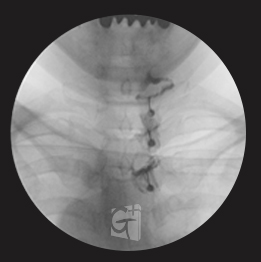

요추 신경성형술

-

꼬리뼈 구멍으로 카테타 삽입

-

척추관 안쪽으로 진입 약물 주입

-

원인부위 염증 제거 및 유착 박리

-

유착박리로 추간공 확보, 신경 압박 감소

-

척추관에서 약물이 잘 퍼져나오는 모습

-

허리 신경 전체를 효과적으로 치료